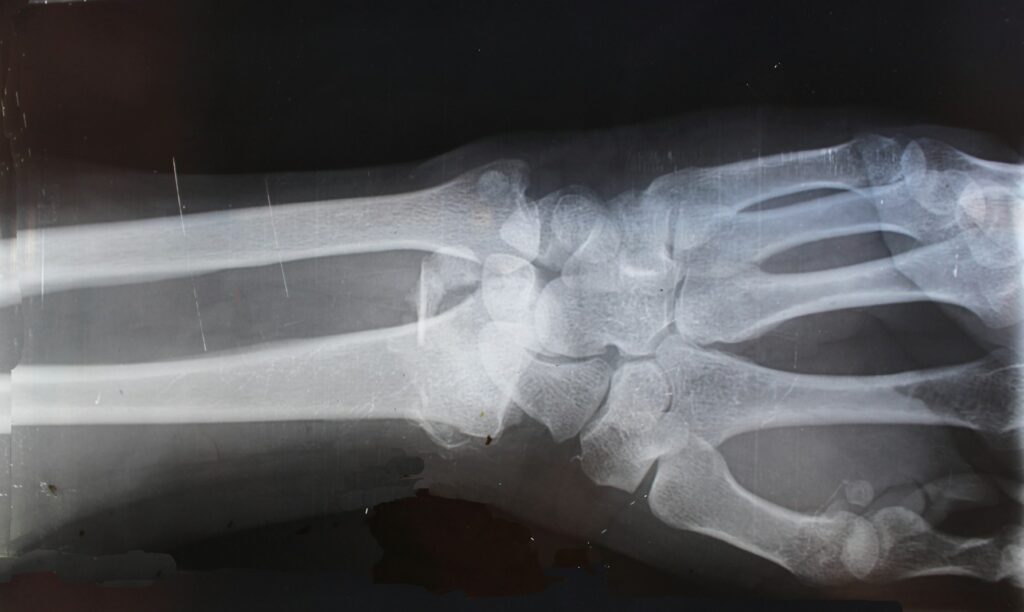

Radiology provides a non-invasive method for examining the internal structures of the body. You might first encounter it through an obstetric ultrasound, then x-rays for diagnosing broken bones as a teenager, and a bone density scan in your later years. Radiological assessments help physicians diagnose and treat various disorders and injuries effectively.

At Medics Clinic, our Radiology department is staffed with certified technologists who perform these diagnostic tests, and virtual radiologist interprets the results with the assistance of Artificial Intelligence. Together, they function as a cohesive team to deliver superior care and imaging services in Accra.

circled check X-Ray